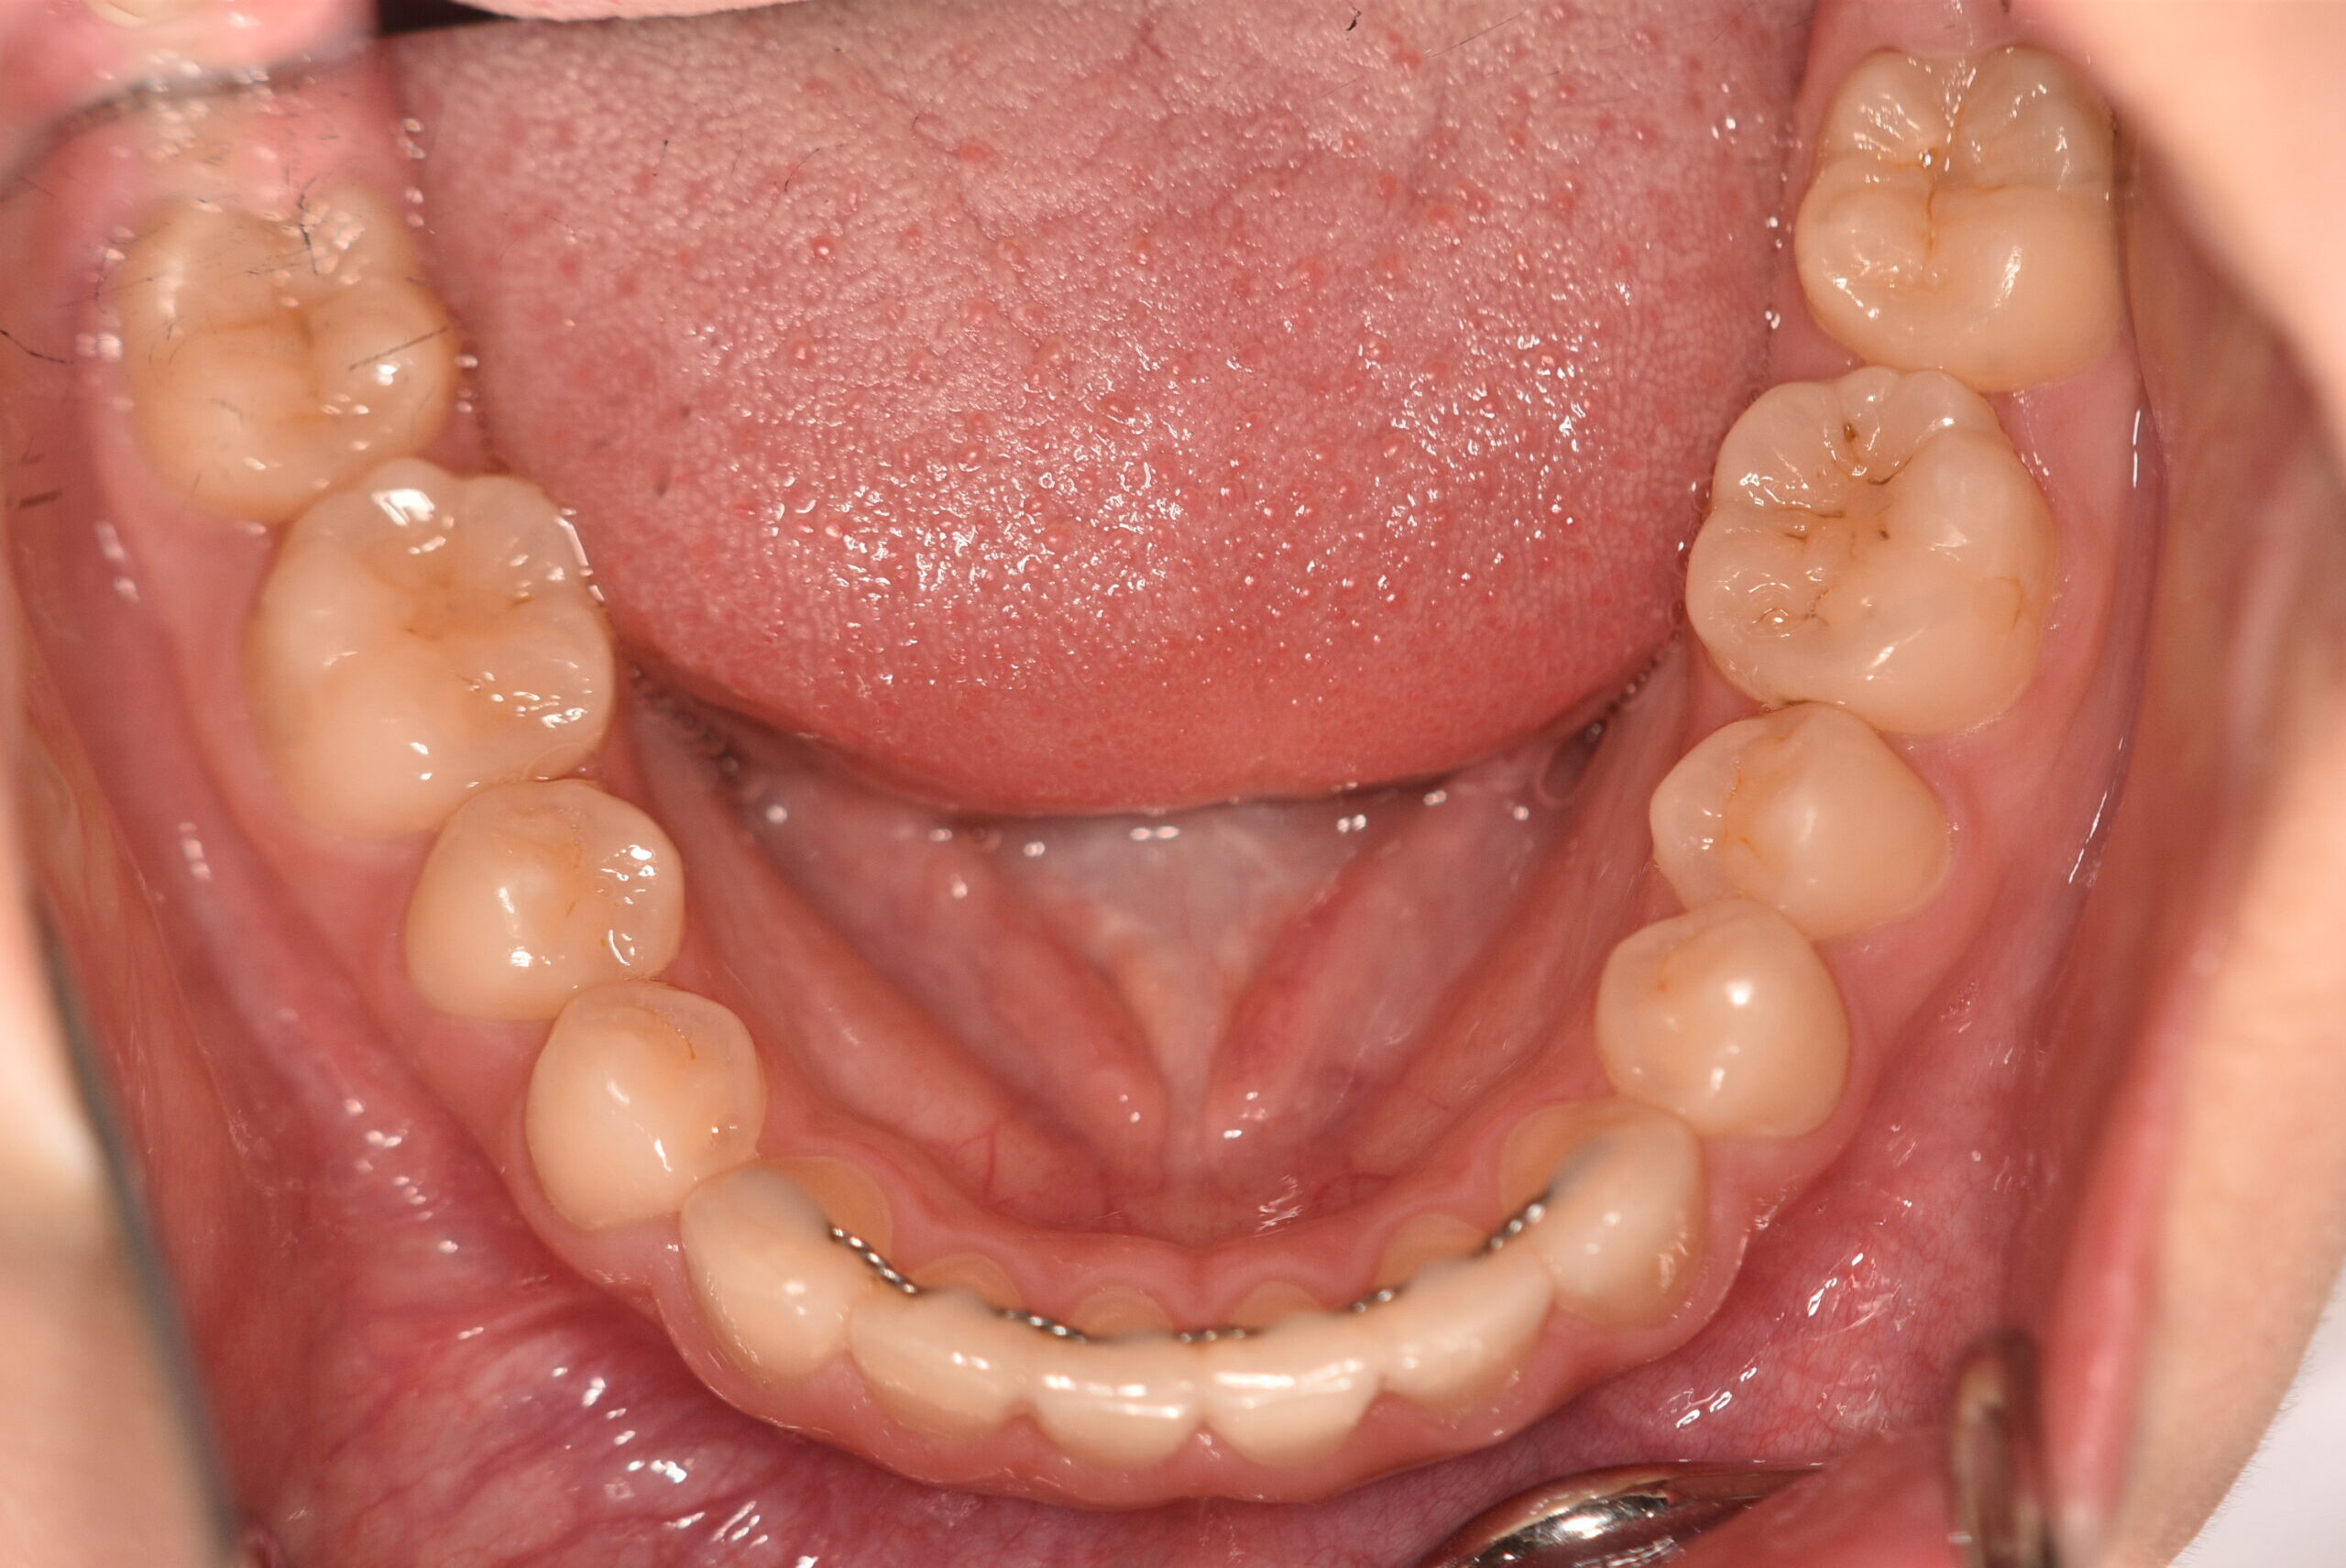

動的治療終了時

症例 症例 症例 症例 症例

永久歯列に交換後、非抜歯の上、セルフライゲーションブラケット装置(デーモンシステム)で歯の配列を行いました。

治療期間は、4年3ヶ月でした。